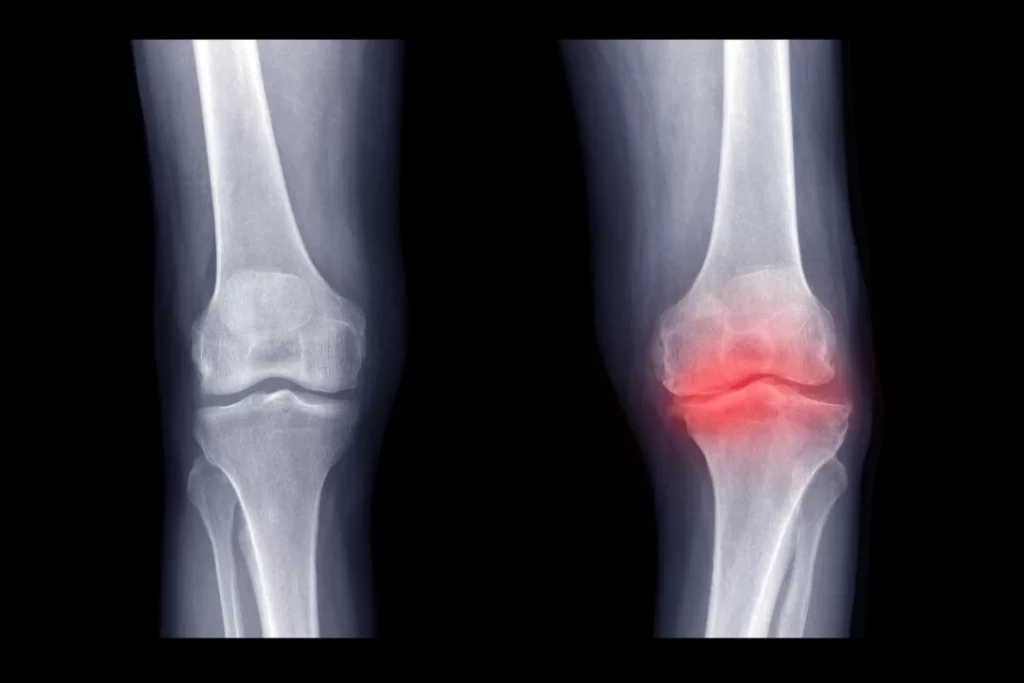

A terapia com campo eletromagnético pulsado (PEMF) mostra-se promissora na redução da dor e na melhora da qualidade de vida de pacientes com osteoartrite.

À medida que a população dos Estados Unidos envelhece, um aumento nas condições articulares agonizantes espreita no horizonte. A principal delas é a osteoartrite, uma doença debilitante causada pela quebra natural da cartilagem.

Uma revisão sistemática recente publicada no Journal of Clinical Medicine lança luz sobre o potencial da terapia de campo eletromagnético pulsado (PEMF), introduzida na prática clínica na década de 1970 com um dispositivo aprovado pela Food and Drug Administration (FDA) dos EUA para ajudar a acelerar a cicatrização de fraturas quebradas para aliviar os sintomas da osteoartrite (OA).

Para a nova revisão, os pesquisadores analisaram 17 ensaios clínicos randomizados e controlados envolvendo 1.197 pacientes com OA submetidos à terapia com PEMF. Eles avaliaram os dados para avaliar a efetividade do PEMF em diferentes áreas anatômicas, com foco nos níveis de redução da dor e na melhora da qualidade de vida dos pacientes.

Os achados sugerem que a terapia com PEMF melhorou significativamente a redução da dor, avaliada por meio da Escala Analógica Visual (EVA) e dos escores do Western Ontario and McMaster Universities Osteoarthritis Index (WOMAC). Os escores da EVA diminuíram em 60% e os escores do WOMAC melhoraram em 42%.

A revisão também observou que os participantes reduziram o uso de medicamentos e melhoraram a função física.

Apesar desses resultados positivos, a revisão destacou a variabilidade na duração do tratamento e nos tipos de dispositivos de PEMF usados, com os autores do estudo pedindo mais investigação e padronização nessas áreas.